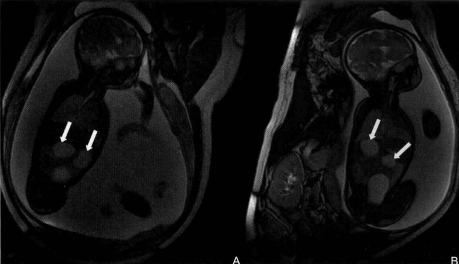

2.MRI表现:在T2WI序列上,表现为胎儿上腹 部可见胃泡及十二指肠扩张积液,积液呈高信号,呈 “双泡征”。见下图: